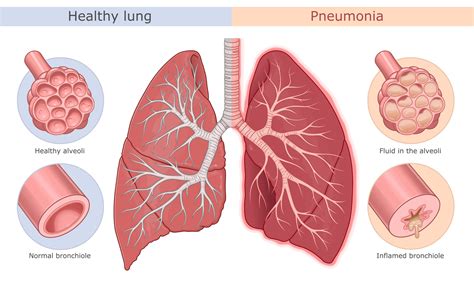

Walking pneumonia, also known as atypical pneumonia, is a mild form of pneumonia caused by bacteria, viruses, or fungi. Unlike typical pneumonia, which often requires hospitalization, walking pneumonia allows patients to continue their daily activities while recovering. The most common cause of walking pneumonia is the bacterium Mycoplasma pneumoniae, but other pathogens like Chlamydophila pneumoniae and viruses can also be responsible.

Understanding Bronchitis

Bronchitis is an inflammation of the bronchial tubes, which carry air to and from the lungs. It can be acute or chronic. Acute bronchitis is usually caused by viruses and resolves within a few weeks, while chronic bronchitis is a long-term condition often associated with smoking or exposure to irritants.